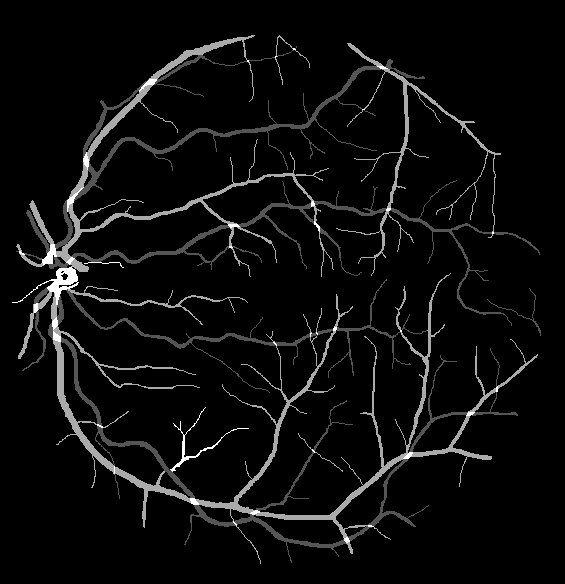

The visual differentiation between arteries and veins can be difficult in some cases, like small vessels with poor contrast and not clearly connected to a specific arterial or venular tree. These cases can be identified with certainty as vessels, but their classification into arteries and veins is uncertain, even for an expert. Additionally, it is common to find crossings between arteries and veins in the retina. Thus, although for these positions either the artery or the vein is above the other, these pixels can be regarded as simultaneously belonging to both types of vessels. This allows to account for continuous arterial and venular trees regardless of crossings below the other one. The identification of these two special situations (uncertain vessels, and vessel crossings) is common in manually annotated retinal vessel classification datasets [38, 42, 43, 44]. Figure 1 shows an example of a ground truth image from the RITE dataset labelled this way, along with its decomposition into arteries, veins, crossings and uncertain vessels.

In addition to this feature, it is also relevant to note that, in this case, the “uncertain” class does not include the vessel crossings, unlike the “uncertain or crossing” class defined in the traditional approach. Instead, in this approach, the vessel crossings are encoded as the superposition of the artery and vein segmentation maps, which should be both indicating positive class for these pixels. In order to do that, the ground truth for each class should be adapted to the output of the network and these restrictions. This can be achieved by considering the vessel crossing regions as positives in both artery and vein segmentation maps, and combining these two maps with the uncertain vessel regions to obtain the vascular tree segmentation map. An example of such an adapted ground truth is shown in Figure 3. Additionally, this setting allows to detect vessel crossings through the intersection (product) of the predicted arteries and veins segmentation masks.

Also, an example of a retinography and its corresponding vasculature segmentation and A/V classification ground truths is depicted in Figure 6.

In order to train the networks following the traditional and MS approaches, the ground truth images from the RITE dataset are adapted, in each case, to the output of the network. In the traditional approach, each pixel of the ground truth is assigned to either background, artery, vein or “uncertain or crossing” class, which comprises both uncertain vessels and crossings. The resulting ground truth is a grayscale image in which each pixel has a numeric label of the class to which it belongs. On the other hand, in the MS approach, each pixel is assigned to any number of the following classes: artery, vein and vessel. In this case, crossings belong to the three classes, and uncertain vessels belong only to the “vessel” class. Background pixels are not assigned to any class. The resulting ground truth is an RGB image in which each channel contains a manual segmentation mask of one of the aforementioned structures. An example of a RITE ground truth adapted to both the traditional and the MS approaches can be found in Figure 7.

Lastly, Figure 13 shows representative examples of the predicted probability maps that were obtained by the trained models using both losses and the enhanced retinographies as input. In each case, the figure depicts the RGB composition of the predicted maps for a better clarity.

Another relevant point that can be observed in the different figures is the beneficial effect of the preprocessing for the A/V classification. As can be seen in Table 3 and Figure 12, the performance of the networks is, in general, better when they are trained using the enhanced images than when they are trained using the original ones. In fact, this improvement can be clearly appreciated in Figure 13, which depicts the probability maps that were predicted by the networks for a RITE-test retinography. When comparing the predictions of the “enhanced” and the “original” alternatives, it can be observed that some manifest classification errors disappear, an thus the arteries and veins continuity is slightly better preserved. Regarding the vessels segmentation, in light of the results, the preprocessing does not lead to such a significant improvement in the networks performance.